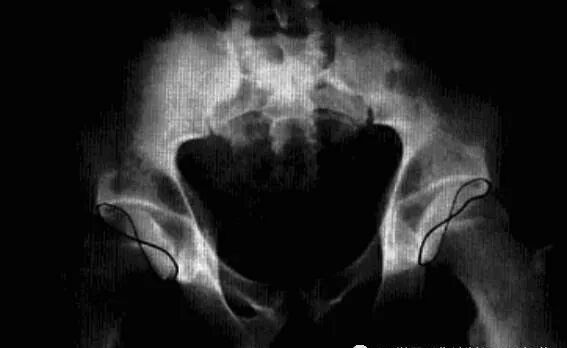

髋关节撞击综合征

也称股骨髋臼撞击综合征,是由于股骨近端和髋臼盂缘间解剖的异常,或解剖正常但长期不正常外力作用于髋关节,导致两者长期不正常接触、碰撞,产生反复的微型创伤致使关节盂缘和关节软骨退变,从而引起慢性髋关节疼痛及髋关节屈曲和内收受限的疾病。分为凸轮撞击和钳夹撞击两个类型。

病理:股骨头软骨呈明显退变现象,关节唇骨化、瘢痕化、体积增大、软骨下撕裂。

临床表现:凸轮撞击多见于喜欢运动的青年男性,钳夹撞击多见于活动较多的女性。典型表现为腹股沟区疼痛,通常在活动或久坐后加剧,呈间歇性,后期呈持续性。病变常呈单侧性,查体时髋关节活动受限,撞击试验阳性。

影像诊断:X线平片是基本检查方法,直立骨盆正位及髋关节侧位片。

平片:①凸轮撞击型,正位片示头颈连接处扁平,呈“左轮枪柄”样畸形,侧位片示股骨头颈凹陷减少,*边缘角变小<16度,②钳夹撞击型,髋臼窝过深,髋臼后倾,呈相交8字征,偏心距缩短<9mm。

CT:三维CT可测量股骨头颈连接处前外侧偏移量减低,股骨头颈联合处前上缘可见骨性突起。

MRI:股骨头颈凹陷减少(α>50°),股骨颈宽度与股骨头半径比率增大,髋臼后倾。盂缘退行性改变,撕裂、囊肿,关节间隙后期出现狭窄,周围肌肉炎症。